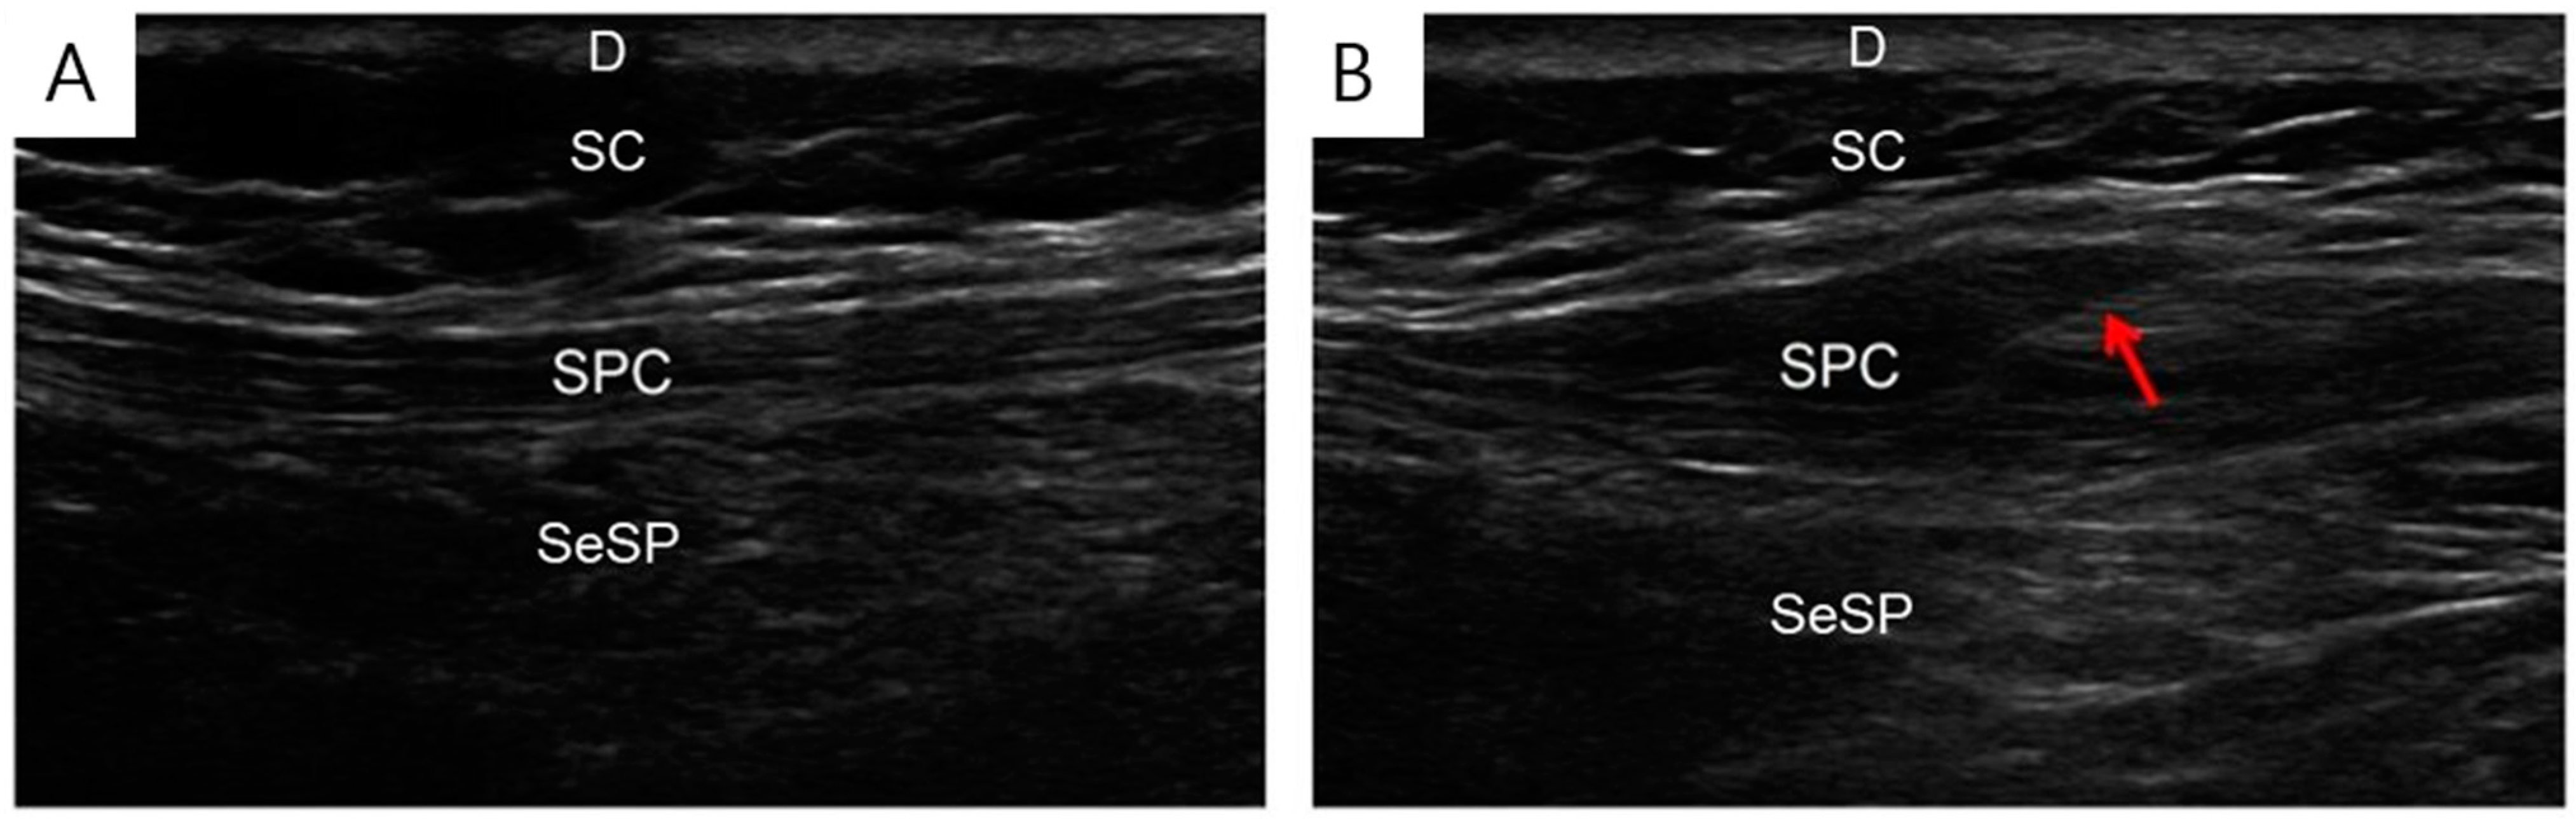

2.3. Intervention